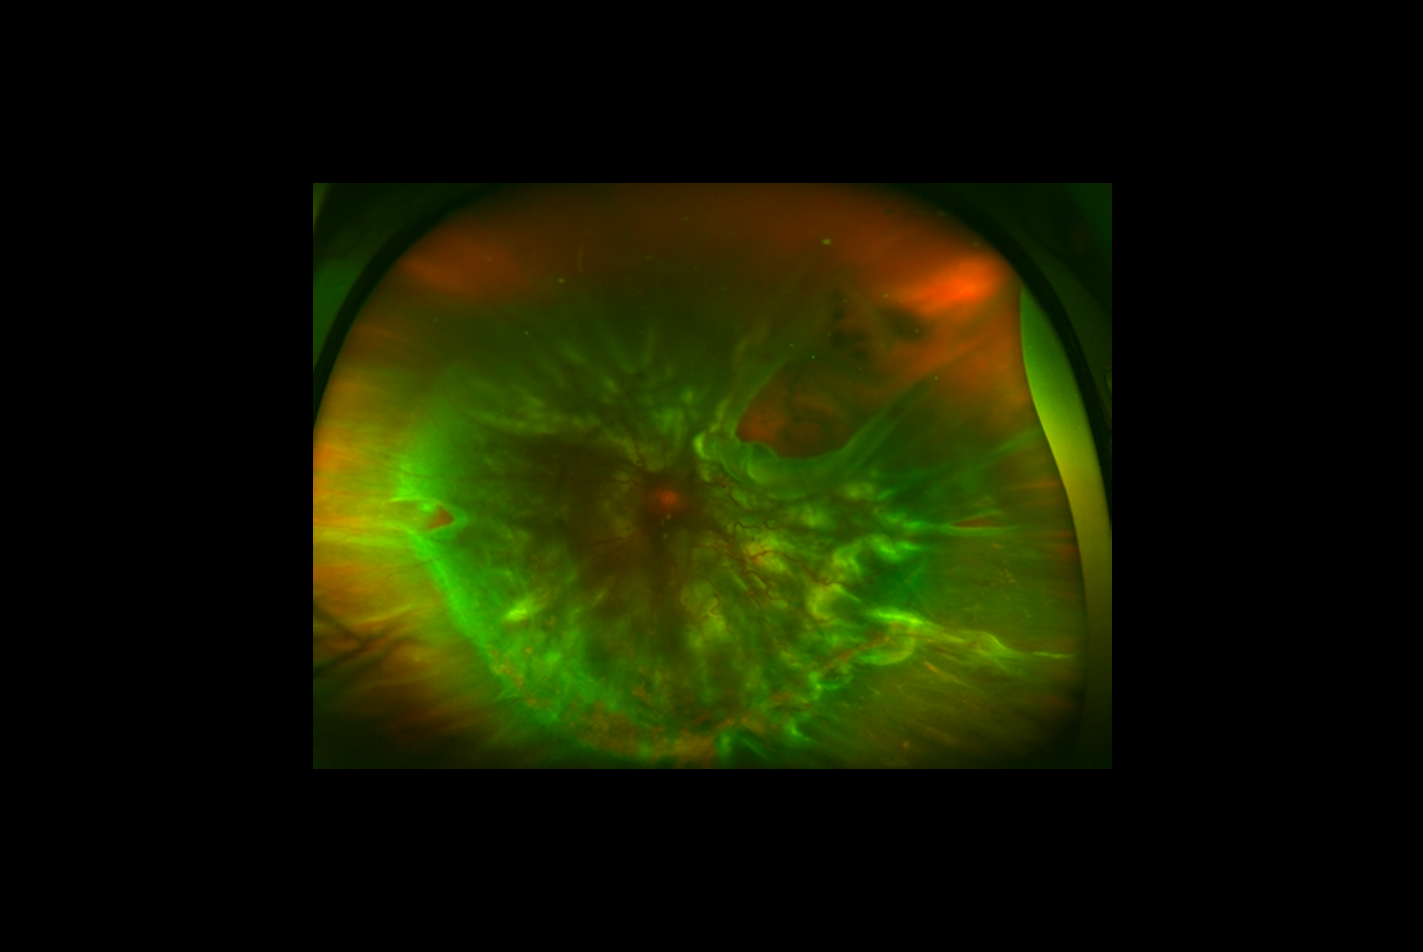

ophtavalmy.frFond D’oeil_Décollement Rétine Supérieur Avec Déchirure Rétinienne

ophtavalmy.frFond D’oeil_Décollement Rétine Supérieur Avec Déchirure Rétinienne